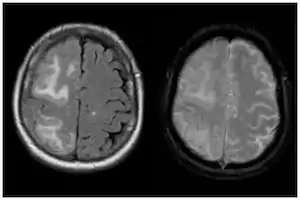

| Two MRI scans demonstrating the difference between ARIA-E (left) and ARIA-H in the parietal region (right) | |